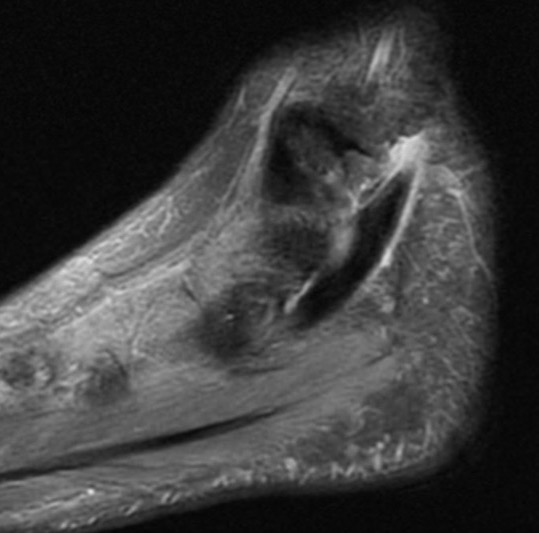

MRI

Tendonitis - fluid around tendon

Tendinopathy - tendon thickening

Tears

Tear tibialis posterior with 10 cm gap